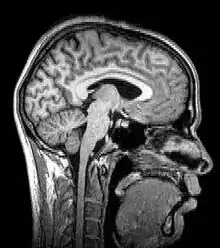

Tomography is imaging by sections or sectioning that uses any kind of penetrating wave. The method is used in radiology, archaeology, biology, atmospheric science, geophysics, oceanography, plasma physics, materials science, cosmochemistry, astrophysics, quantum information, and other areas of science. The word tomography is derived from Ancient Greek τόμος tomos, "slice, section" and γράφω graphō, "to write" or, in this context as well, "to describe." A device used in tomography is called a tomograph, while the image produced is a tomogram.

Although MRI (magnetic resonance imaging), optical coherence tomography and ultrasound are transmission methods, they typically do not require movement of the transmitter to acquire data from different directions. In MRI, both projections and higher spatial harmonics are sampled by applying spatially-varying magnetic fields; no moving parts are necessary to generate an image. On the other hand, since ultrasound and optical coherence tomography uses time-of-flight to spatially encode the received signal, it is not strictly a tomographic method and does not require multiple image acquisitions.